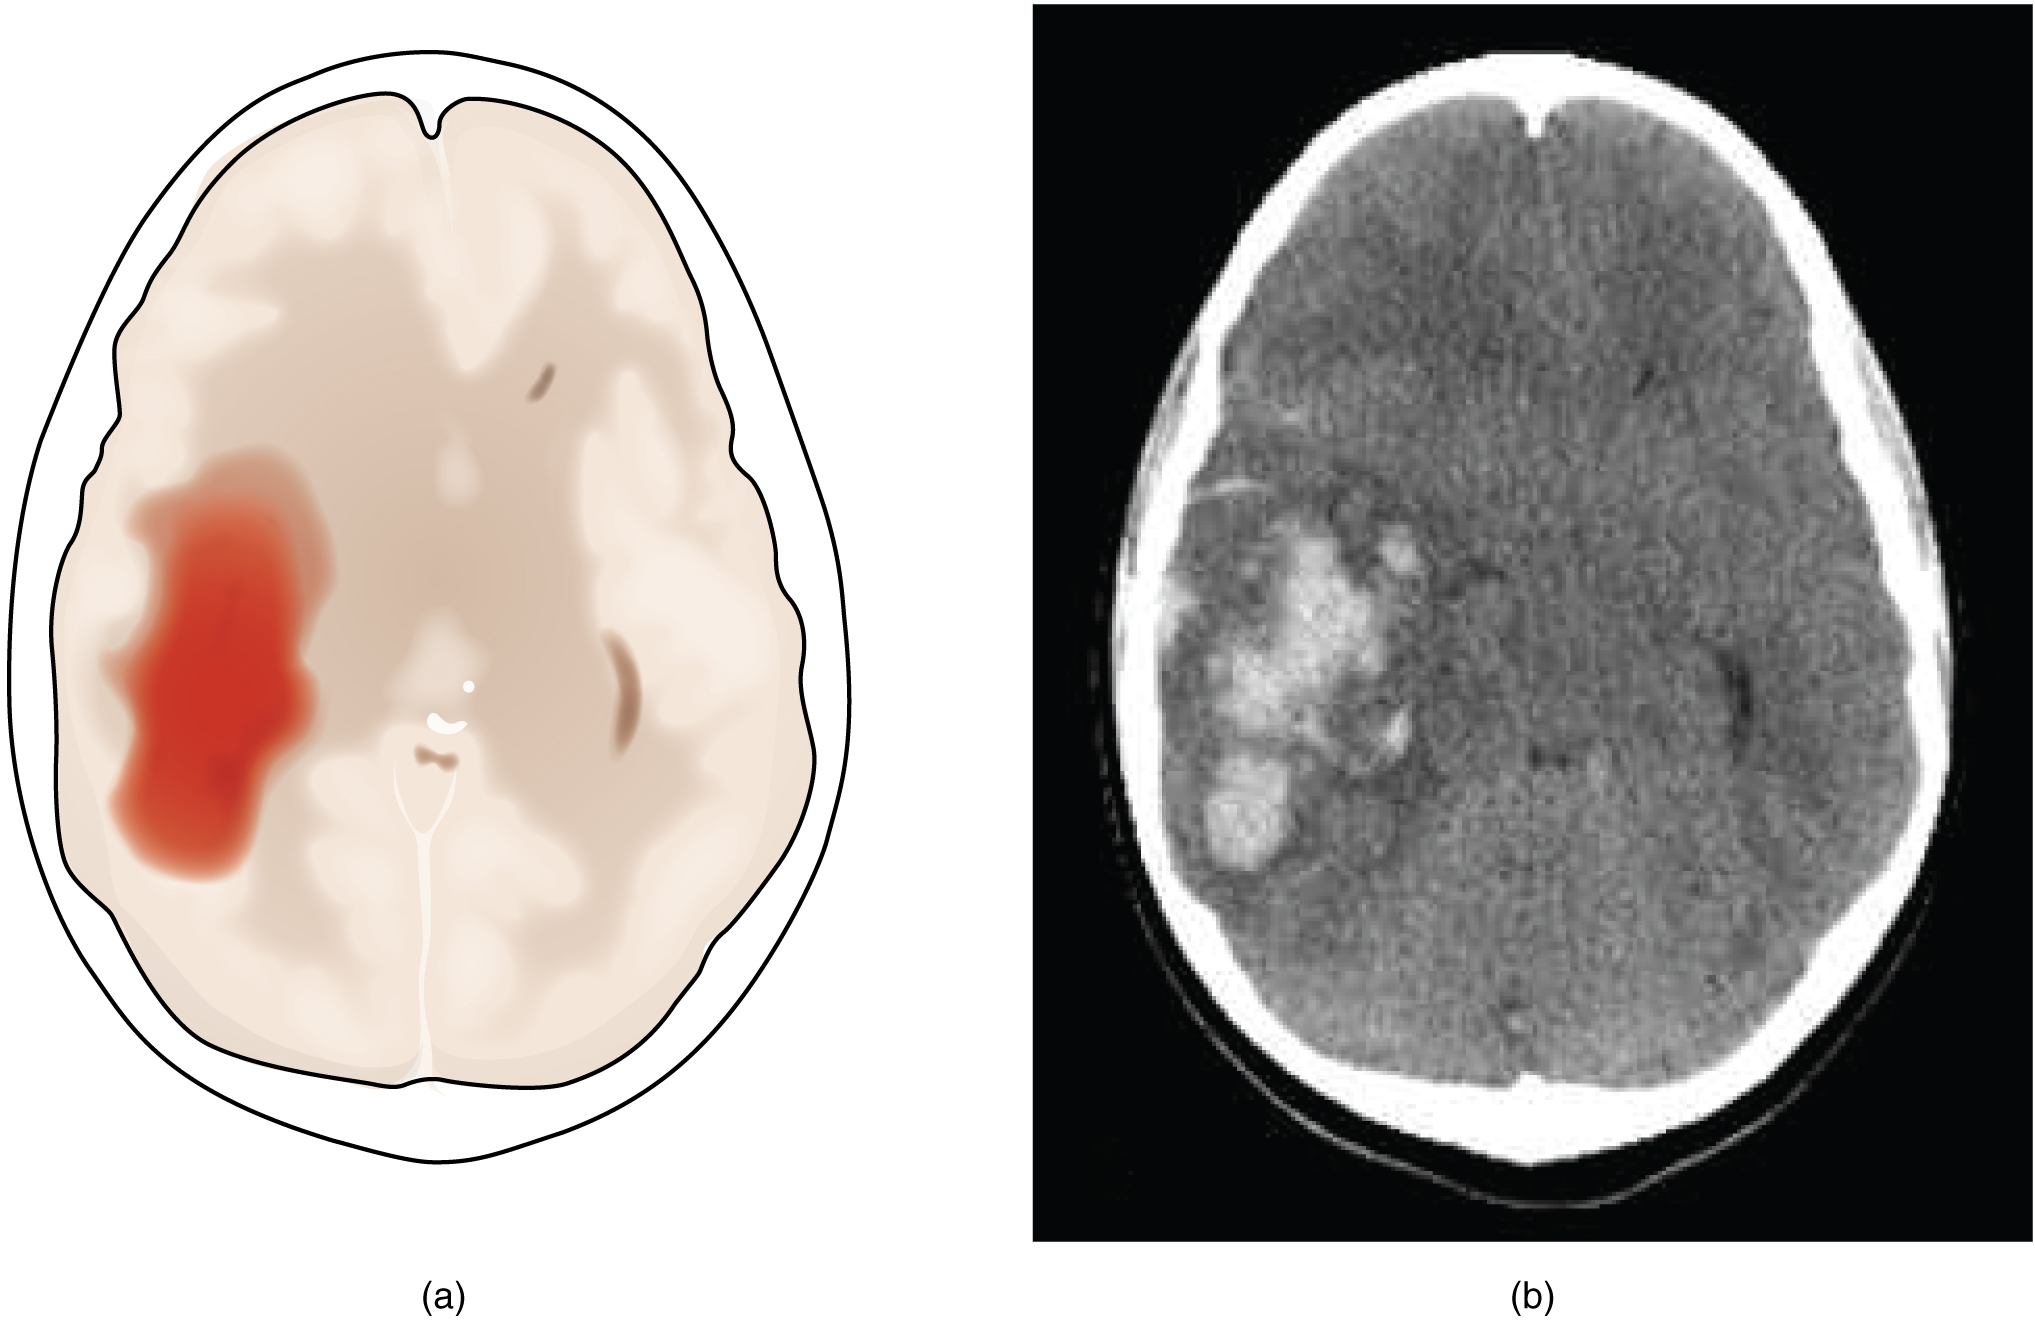

A hemorrhagic stroke is bleeding into the brain because of a damaged blood vessel. Accumulated blood fills a region of the cranial vault and presses against the tissue in the brain (Figure 14.2.3). Physical pressure on the brain can cause the loss of function, as well as the squeezing of local arteries resulting in compromised blood flow beyond the site of the hemorrhage. As blood pools in the nervous tissue and the vasculature is damaged, the blood-brain barrier can break down and allow additional fluid to accumulate in the region, which is known as edema.